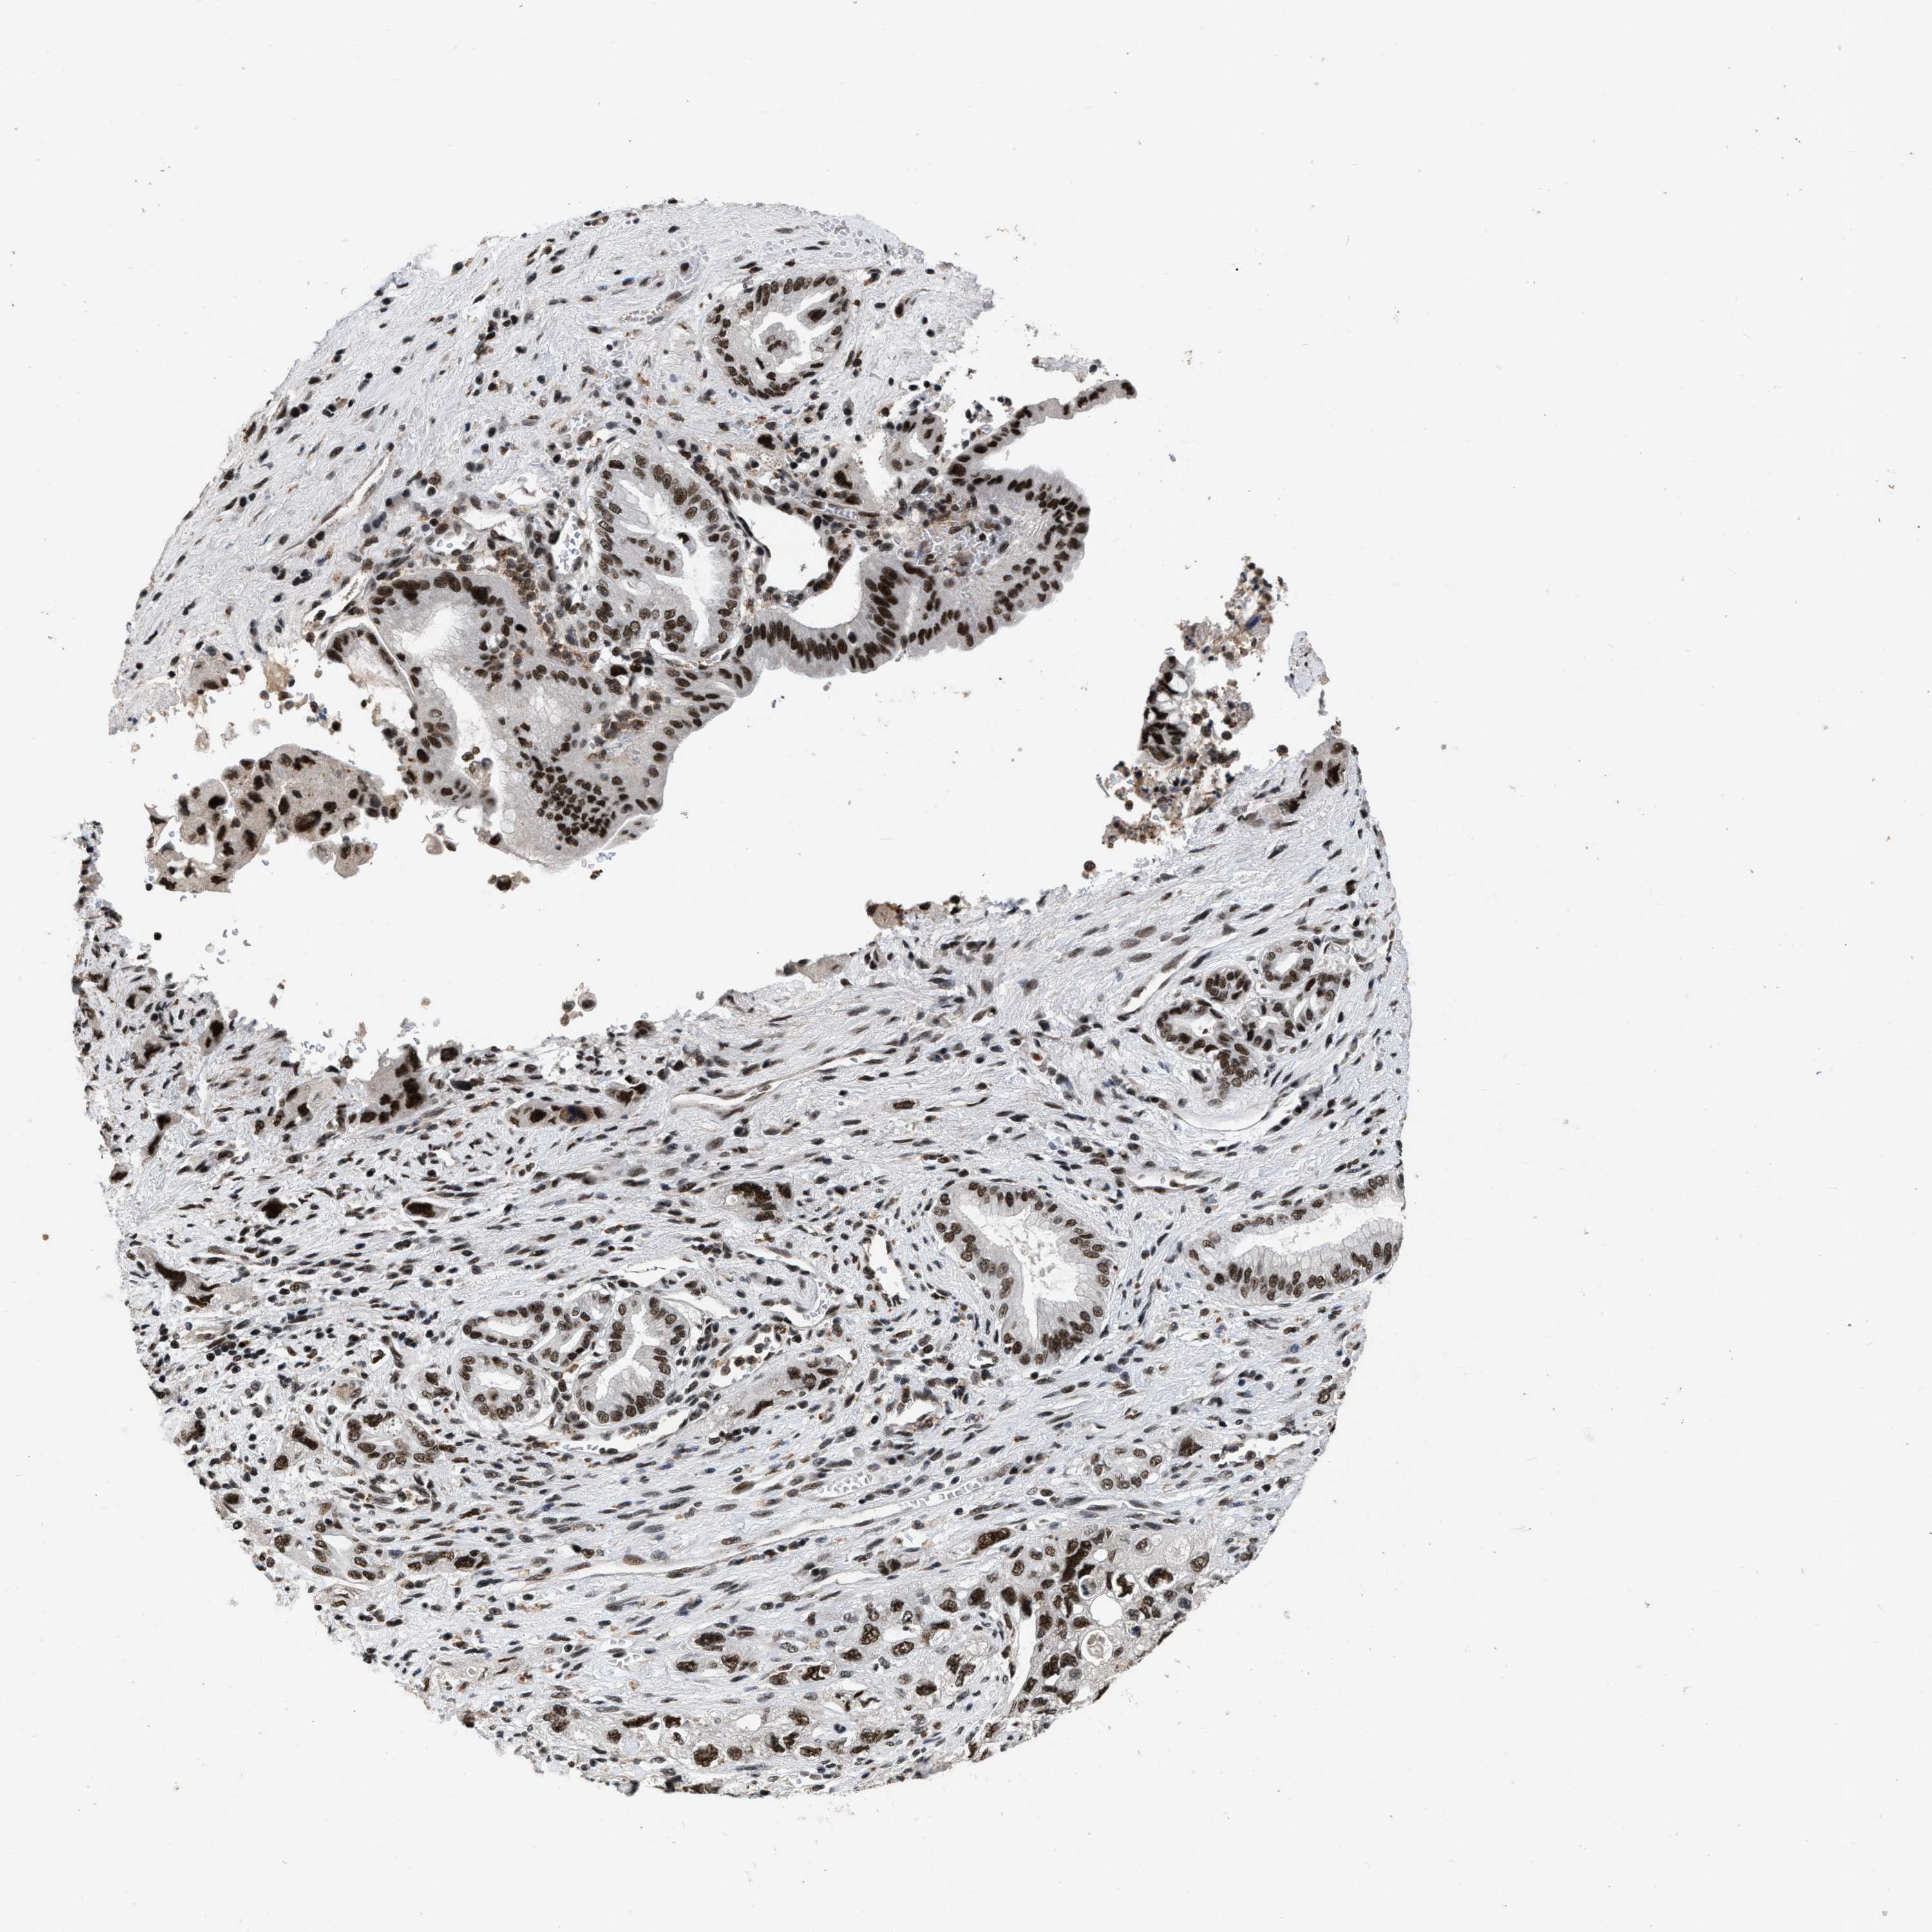

PANCREATIC CANCER - Protein expressioni

A mouse-over function shows sample information and annotation data. Click on an image to view it in a full screen mode. Samples can be filtered based on level of antibody staining by selecting one or several of the following categories: high, medium, low and not detected. The assay and annotation is described here.

Note that samples used for immunohistochemistry by the Human Protein Atlas do not correspond to samples in the TCGA dataset.

Antibody stainingi

Antibody staining in the annotated cell types in the current human tissue is reported as not detected, low, medium, or high, based on conventional immunohistochemistry profiling in selected tissues. This score is based on the combination of the staining intensity and fraction of stained cells.

Each image is clickable and will lead to virtual microscopy that enables deeper exploration of all samples and also displays staining intensity scores, fraction scores and subcellular localization as well as patient and tissue information for each sample.

Antibody HPA018248

Antibody HPA019127

Antibody CAB009196

Staining

High

Medium

Low

Not detected

Adenocarcinoma, NOS

Adenocarcinoma, metastatic, NOS